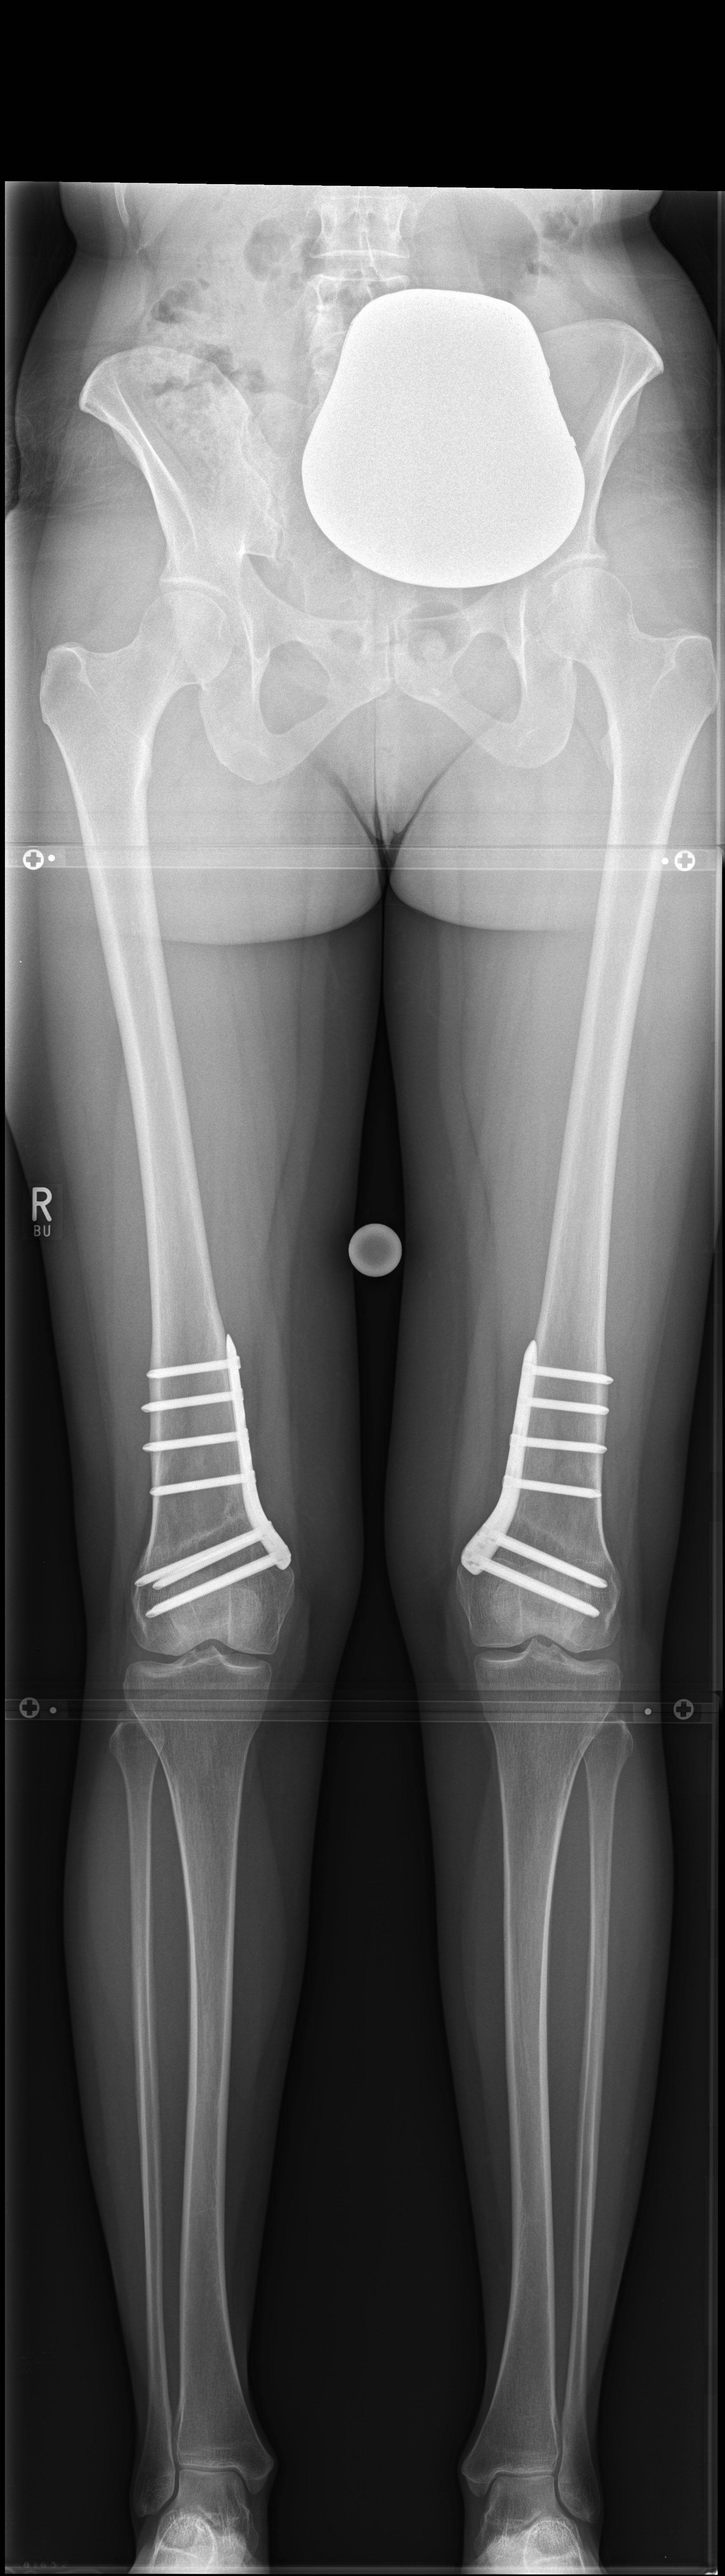

A 33-year-old woman complained of pain in the lateral compartment after a normal working day. Sports activities were no longer possible. Free range of motion (ROM: 0/0/150°), ligaments in sagittal, and coronal planes were stable. There was no effusion. The patient had valgus deformity which was corrected with a distal femoral osteotomy.

Showcasing a distal femur osteotomy case